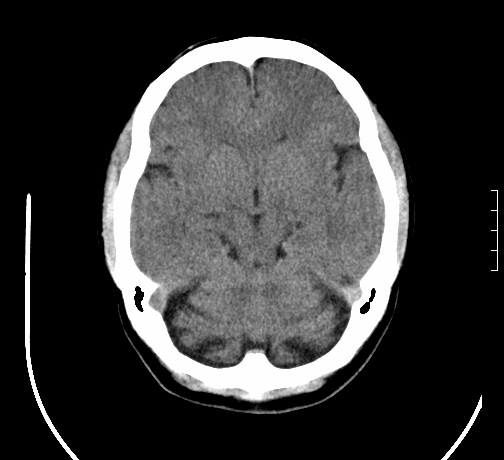

女,28岁,幼时有癫痫,常有发作,服药后可几月不发作,走路不稳3-4月,加重一月。

小脑发育畸形?

小脑萎缩。

考虑小脑发育不良,建议mri检查。

患者出现走路不稳是近几个月的事,而癫痫则有幼时就有,常发,则会常服药,癫痫药可引起小脑综合症,小脑萎缩,而小脑发育不良的主要症状不是癫痫

考虑癫痫,长期间断发服抗癫药,导致小脑综合症,小脑萎缩

考虑小脑发育不良伴小脑萎缩,建议mri检查。

小脑萎缩,原因待查,建议mri检查。

考虑小脑发育不良伴小脑萎缩,建议mri检查

考虑药物性小脑萎缩